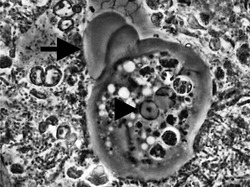

| Entamoeba gingivalis from periodontal pocket [1] | |

It is found in the mouth[5] inside the gingival pocket biofilm near the base of the teeth, and in periodontal pockets.[1] Entamoeba gingivalis is found in 95% of people with gum disease and rarely in people with healthy gums.[6][7] Cyst formation is not present; therefore transmission is direct from one person to another by kissing, or by sharing eating utensils. Only the trophozoites are formed and the size is usually 20 micrometers to 150 micrometers in diameter. Entamoeba gingivalis have pseudopodia that allow them to move quickly and phagocytise the nucleus of polynuclear neutrophils by exonucleophagy in periodontal disease.[8] Their spheroid nucleus is 2 micrometers to 4 micrometers in diameter and contains a small central endosome. There are numerous food vacuoles, which consists mostly of phagocytised PMN nucleus, blood cells, and bacteria. It also causes pyorrhoea.

Media